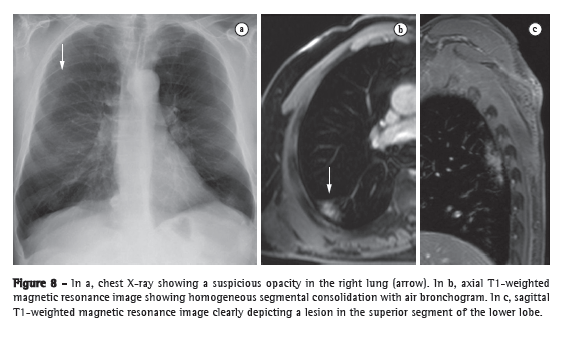

Patients with pneumonia

The various features of pneumonia, such as ill-defined nodules, ground-glass opacities, and consolidations, can be easily detected and differentiated with MRI. In chest X-ray, extremely small nodules and calcifications pose great challenges because of the thickness of the slice and the low intensity of the signal. As a follow-up tool, MRI is recommended over CT, in order to avoid excessive exposure to ionizing radiation. Figure 8 shows a comparison between a chest X-ray and MRI scans of the same chest. The sensitivity of T2-weighted sequences and the potential of contrast-enhanced T1-weighted sequences can greatly facilitate the differential diagnosis.(36) In addition, incipient complications, such as pericardial effusion, pleural effusion, empyema, and lung abscess, are easily recognized on MRI scans. In immunocompromised patients, MRI is nearly as accurate as is CT for the detection of pulmonary abnormalities.(8)